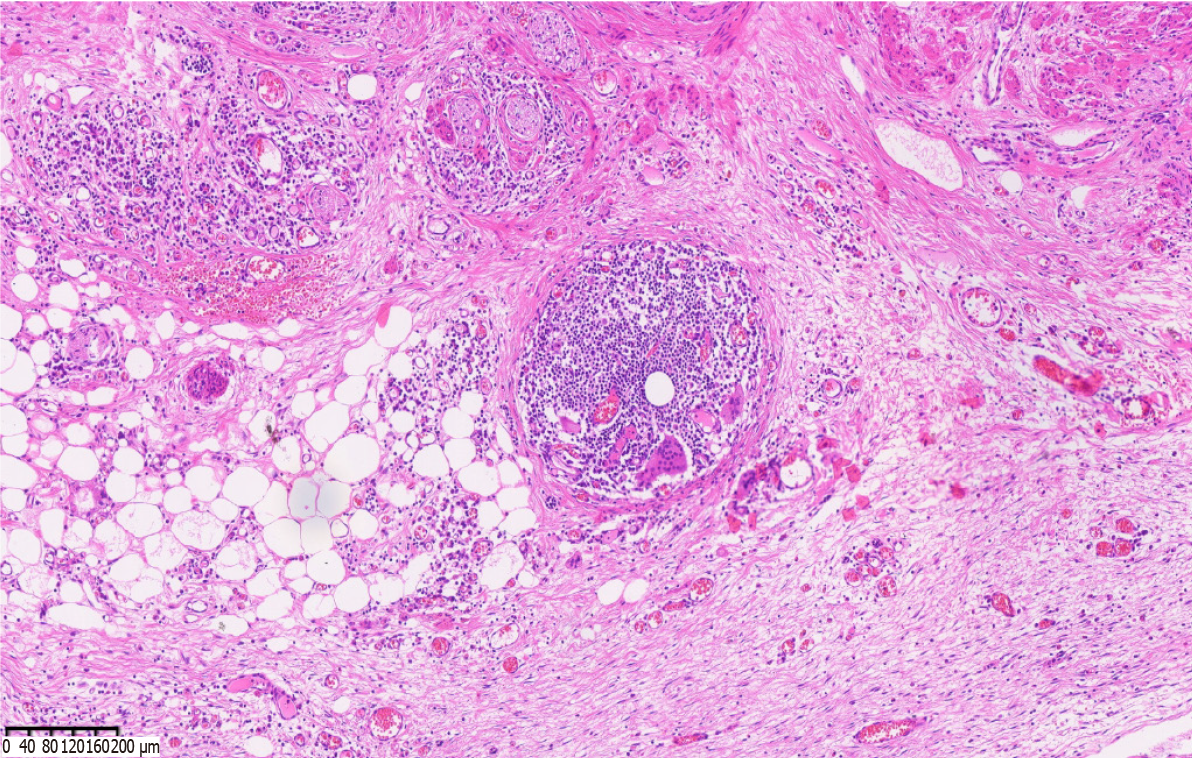

Core Tip: We report an extremely rare case of chronic appendicitis caused by a chicken bone in the appendix. The patient was 35-year-old woman, and had a long-term abdominal pain of unknown cause. Abdominal computed tomography examination suggested foreign bodies in the appendix, and laparoscopic appendectomy was performed. The postoperative specimen revealed chicken bones in the appendix cavity, and histopathological examination confirmed chronic appendicitis with giant cell reaction of foreign bodies. The patient recovered and was followed up for two months without abdominal pain.

Chronic appendicitis caused by foreign bodies has not been reported to date. We report an extremely rare case of chronic appendicitis caused by foreign bodies in the appendix. The cause of the patient's long-term abdominal pain was still unclear, and she was repeatedly treated in several hospitals. Abdominal color ultrasound examination indicated that there was coprolith in the appendix, the appendix was normal structurally, and the degree of abdominal pain was mild, so surgery could not be performed. After empirical antibiotic treatment, the patient's abdominal pain was gradually relieved, but abdominal pain often recurs. Other reasons, such as chronic enteritis, chronic pelvic inflammation, etc. which may cause chronic abdominal pain were excluded. Abdominal CT examination revealed a high-density image in the appendiceal cavity. According to radiologists, foreign bodies in the appendix were considered instead of coprolith, and laparoscopic appendectomy was performed upon the request and consent of the patient. Postoperative incision of the appendiceal specimen revealed chicken bones in the appendiceal cavity. The patient recovered and was discharged after surgery. Abdominal pain did not recur during 2 months follow-up. Therefore, it is particularly important that we carefully assess imaging findings and multidisciplinary diagnosis when facing atypical symptoms.